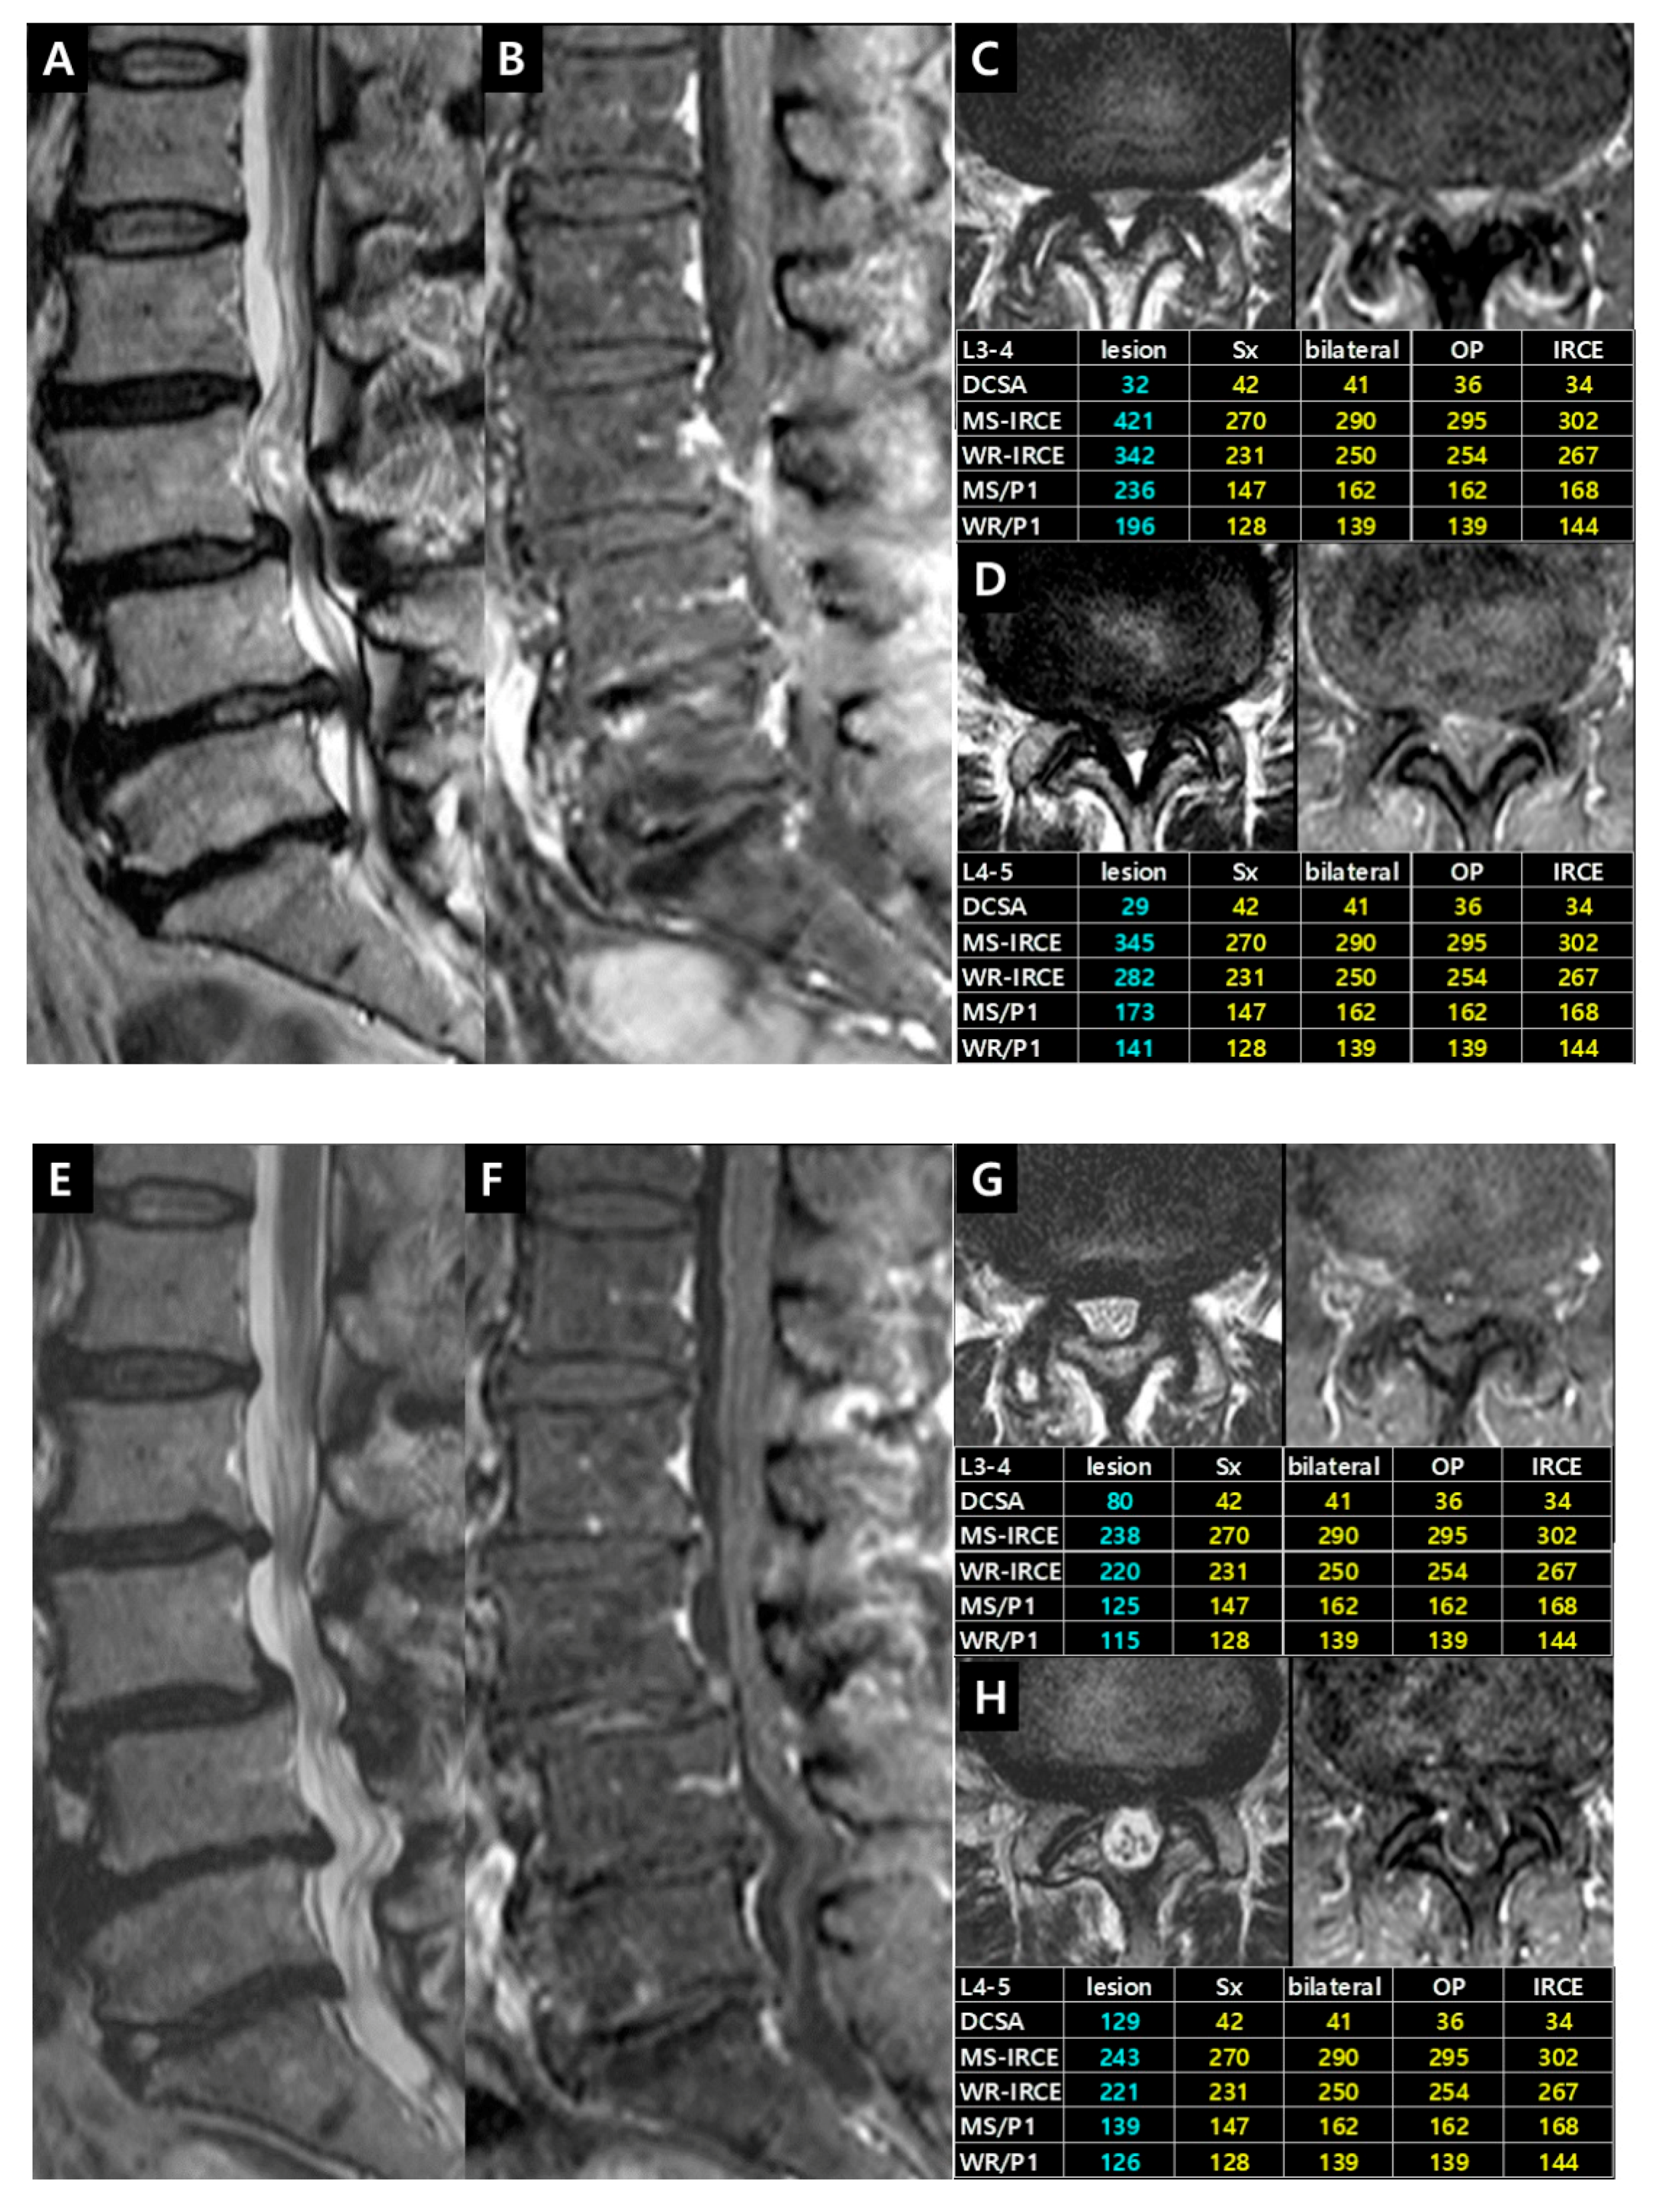

Case 3. Patient (female, 74 years) had complained of pain in bilateral lower buttock and posterolateral thigh for 2 years. The pain was aggravating for 3 months. This case indicated the sequential treatment algorithm performing interventional procedures and decompressive surgeries in the multi-level lumbar stenosis (Figure 11).

Figure 11. Illustrative Case 3. (A,B) T2-weighted and enhanced fat-suppressed T1-weighted sagittal images showed central stenosis on the L2–3, L3–4 and L4–5 level. Axial images revealed higher signals and enhancement parameters on (C) L2–3 and (D) L3–4 level than (E) L4–5 level. The interlaminar injection was performed on (F) L3–4 level at first. Symptoms improved remarkably; (G) Subsequent injection on L2–3 level also improved the pain. (H,I) After L2 and L3 dome laminoplasties, all symptoms disappeared. One week later, follow-up axial images demonstrated the expansion of the thecal sac and the disappearance of IRCEs on (J) L2–3 and (K) L3–4 level. The decrease of enhancement parameters indicated the immediate improvement after surgery.